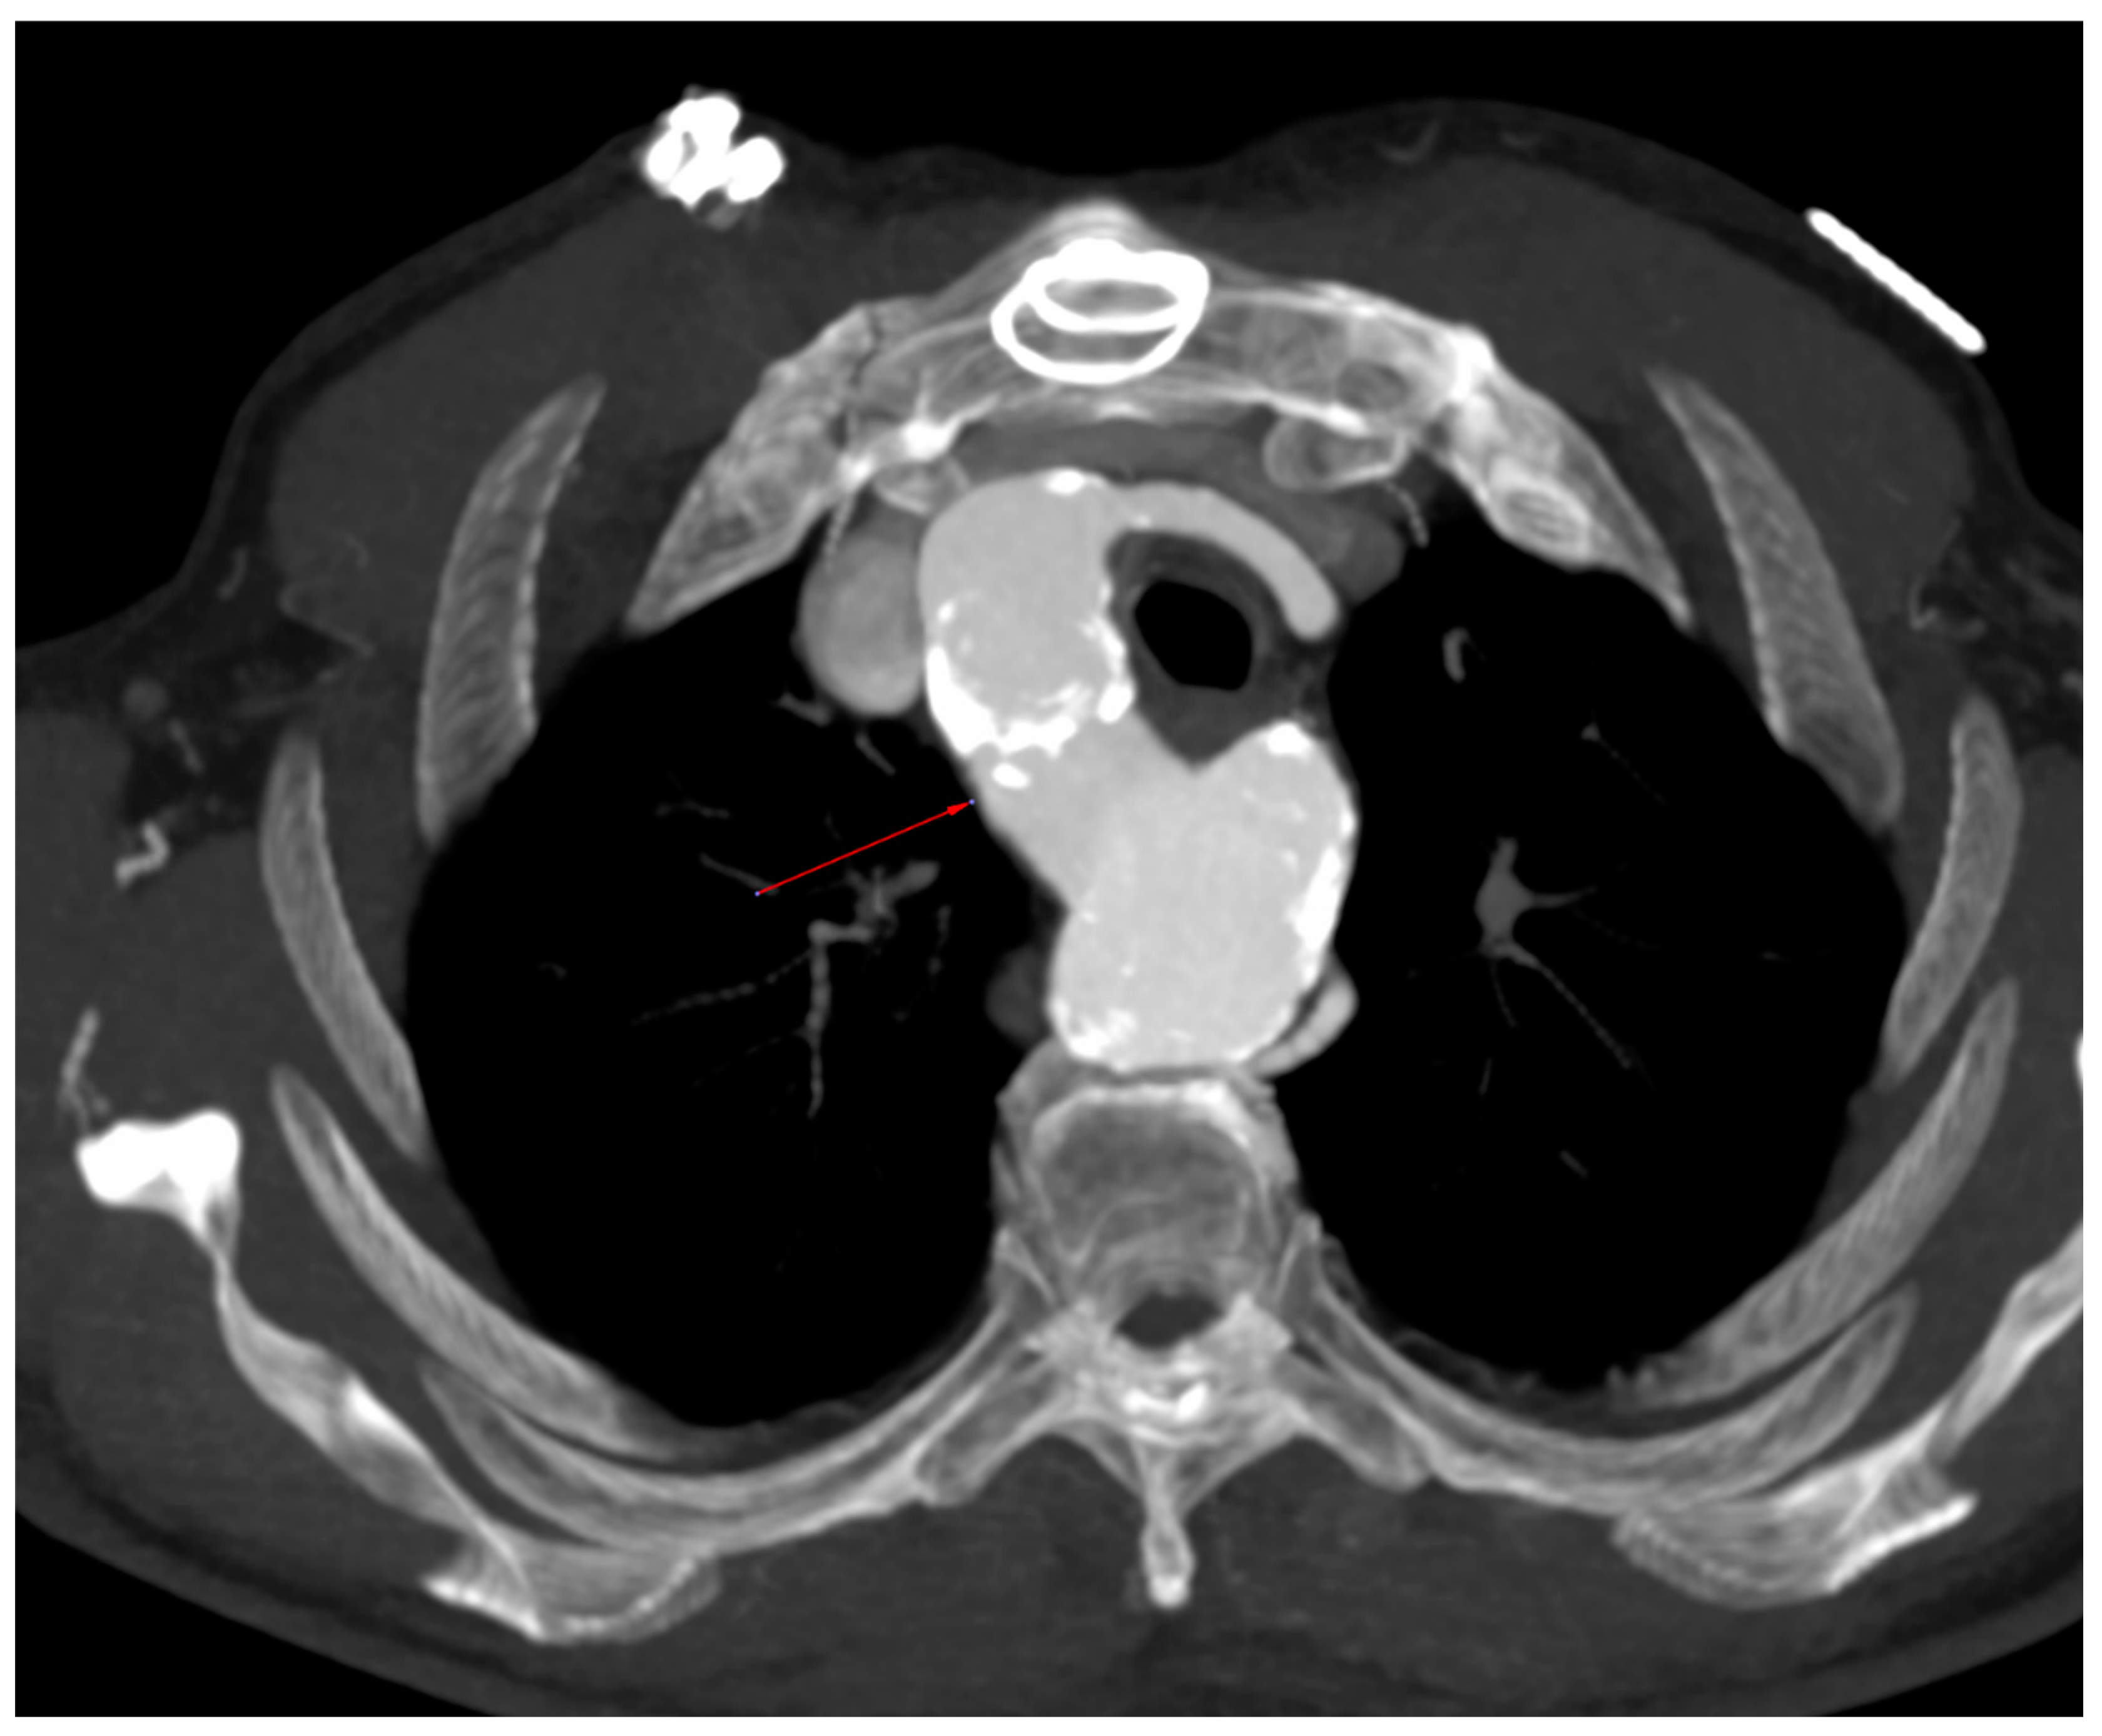

- Incidental vascular finding No. 1: Persistent Left Superior Vena Cava with Absent Right Superior Vena Cava.